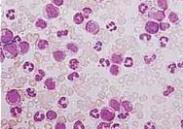

药物性狼疮

628健康网为您分享有关药物性狼疮的症状,药物性狼疮的治疗方法,药物性狼疮的预防知识,药物性狼疮的症状图片,药物性狼疮...

铅中毒

628健康网为您分享有关铅中毒的症状,铅中毒的治疗方法,铅中毒的预防知识,铅中毒的症状图片,铅中毒吃什么药,铅中毒怎么治...

中毒性休克综合征

628健康网为您分享有关中毒性休克综合征的症状,中毒性休克综合征的治疗方法,中毒性休克综合征的预防知识,中毒性休克综合...